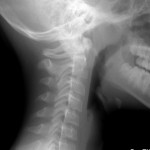

Rö:

– Steilgestellte HWS,

– Bogenschlußstörung C1 bei Hypoplasie des arcus dorsalis

– C2 in kyphotischer Stellung, Dens schief

Diese Konfiguration (sog. Dens recurvatus) ist ein Anteflexionshemmnis. Hier – noch mehr als ohnehin – ist ein Schrägpult für die Hausaufgaben anzuraten.

In diesem Alter kann man getrost davon ausgehen, dass sich das noch anpaßt, nachdem jetzt die Blockierung gelöst wurde und die Kopfgelenke sich wieder frei bewegen können. Man wird hier in 2-3 Jahren eine Kontrollaufnahme machen und dann wohl einen weniger gekippten Gelenkspalt C1/C2 antreffen.